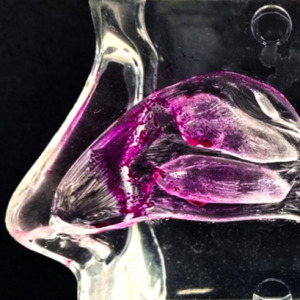

Product Technologie platform for small and large molecules

HWI technology platform provides innovative formulations for small and large molecules. It offers interesting solutions for fast and cost-efficient development, for example, for parenteral and nasal application of poorly soluble active ingredients

Product Inhalation Drug Product Development Services

Inhalation Drug Development Services: With over 35 years of experience, our team supports the development of orally inhaled and nasal drug products (OINDPs), helping clients bring effective respiratory therapies to market. This includes formulation, stability, testing, product performance testing, in vitro...